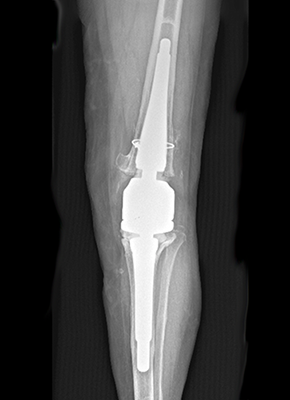

Case Studies

With more than 40,000 individual solutions during the last 50 years, we have been able to gain a lot of experience in this field. We already provided successful solutions for nearly every anatomical region of the human body. See some of our case studies below…